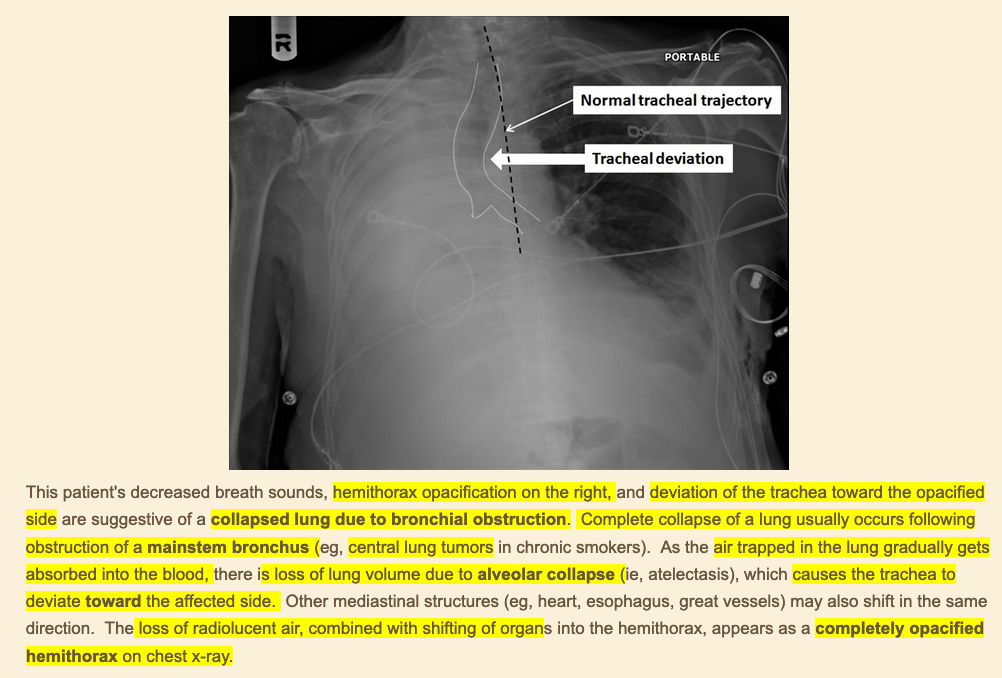

diagnosis?

clinical presentation